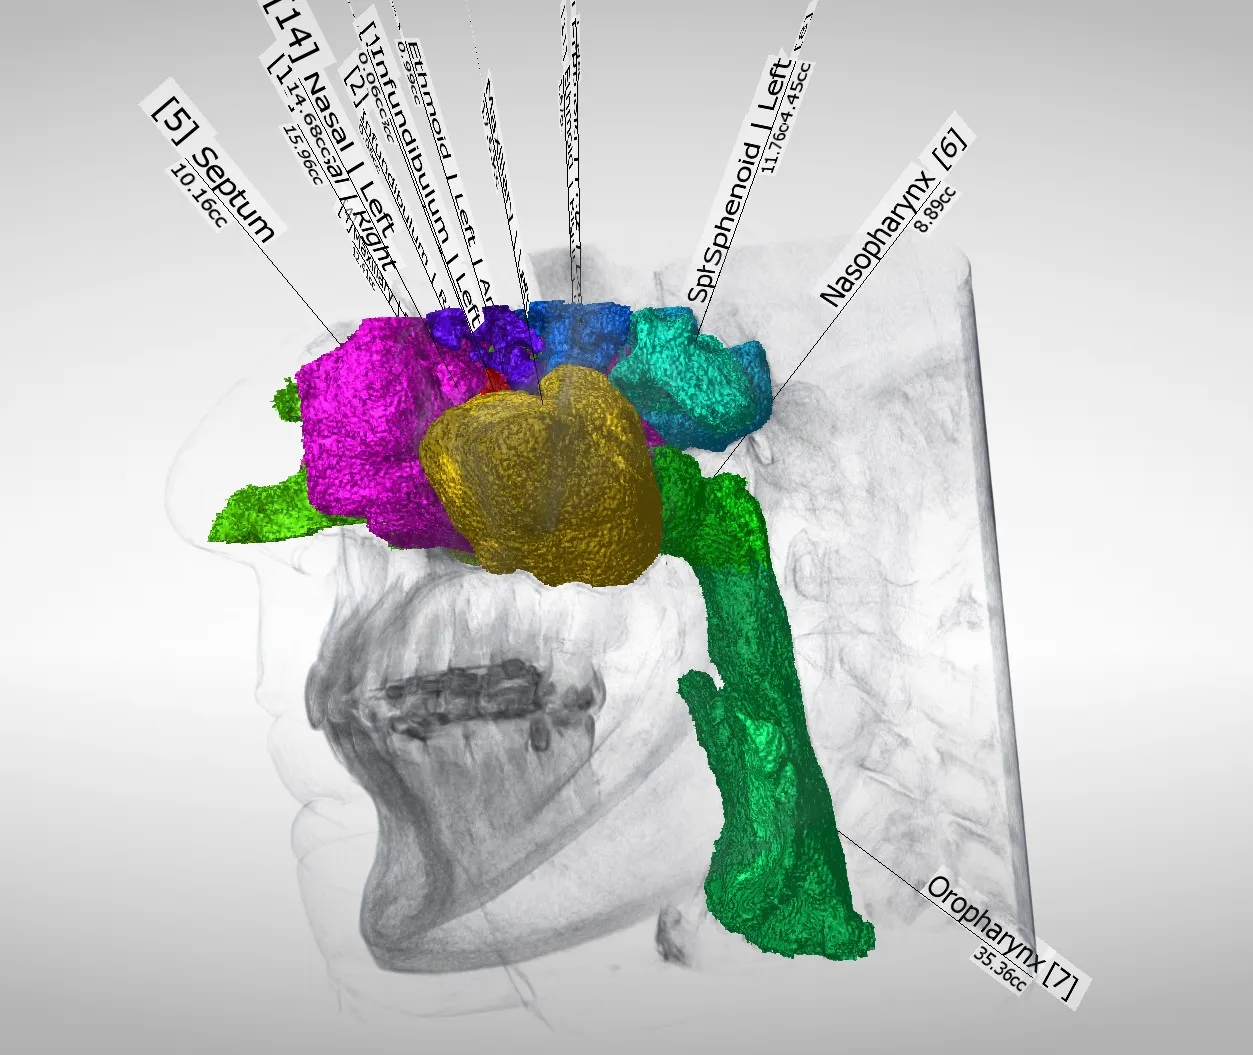

Airway Anatomy Segmentation Review

X-ray Cone Beam CT (CBCT) sagittal slice view of segmentation of human airway anatomy